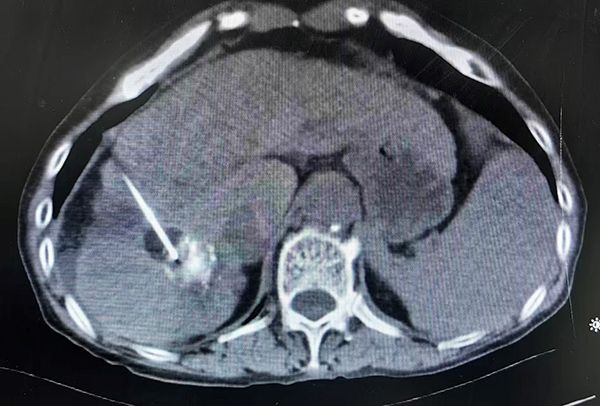

消融后CT

手术当日,介入医学科主任张应战主刀,团队凭借CT影像引导技术,将特制的消融探针精准穿刺至肿瘤内部。随后,利用氩气在针尖急速膨胀产生极低温(约-166℃),将肿瘤组织瞬间冻结成“冰球”,彻底摧毁癌细胞,再通过氦气复温,形成冷热循环,确保肿瘤细胞完全灭活。术中影像实时显示,消融范围完全覆盖病灶,边缘清晰,对周围正常组织影响极小。整个手术全程无痛、微创、精准、高效,患者耐受良好。